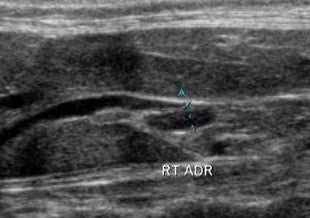

This session will help you optimize your imaging of exotic small mammals. We will discuss interpretation and anatomic variations. A series of cases will be used to demonstrate abnormalities and clinical presentations to help you in practice.

Exotics/Radiology

Presented by Natalie Antinoff DVM, DABVP (Avian)